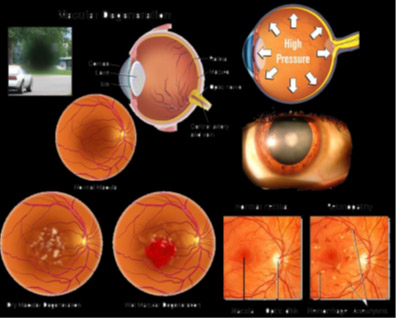

16. Protect your eyes from damage due to ultraviolet-induced

Spirulina for Eye Health

| Spirulina is a rich dietary source of zeaxanthin, a xanthophyll, which are substances similar to carotenes, the proeye compounds. | |||||||||

| Help protect your eyes from damage due to ultraviolet-induced oxidation of lipid membranes and high blood glucose level by slowing down the oxidation and thereby helping prevent degeneration of macula. | |||||||||

| Thus, its intake may have benefit in reducing risk of glaucoma, cataract and age-related macular degeneration. |